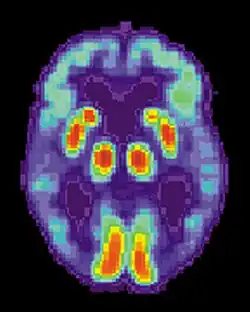

Аппаратура SPECT- и PET-визуализации при её доступности может быть использована для подтверждения диагноза совместно с другими методами оценки, включающими анализ ментального статуса[127]. У людей, уже страдающих от деменции, SPECT, по некоторым данным, позволяет более эффективно дифференцировать болезнь Альцгеймера от других причин, по сравнению со стандартным тестированием и рассмотрением анамнеза[128]. Возможность наблюдать отложения бета-амилоида в мозге живых людей появилась благодаря созданию в Питтсбургском университете Питтсбургского состава B (PiB), связывающегося с амилоидными отложениями при введении в организм. Короткоживущий радиоактивный изотоп углерод-11 в соединении позволяет определять распределение этого вещества в организме и получать картину амилоидных отложений в мозге больного с помощью ПЭТ-сканера[129]. Показано также, что объективным маркером болезни может быть содержание бета-амилоида либо тау-белка в спинномозговой жидкости[130] и крови[131]. Эти два новых метода вызвали предложения о разработке новых диагностических критериев[114][120]. Другие препараты для PET-визуализации: флорбетапир, флутеметамол, флорбетабен, флортауципир.